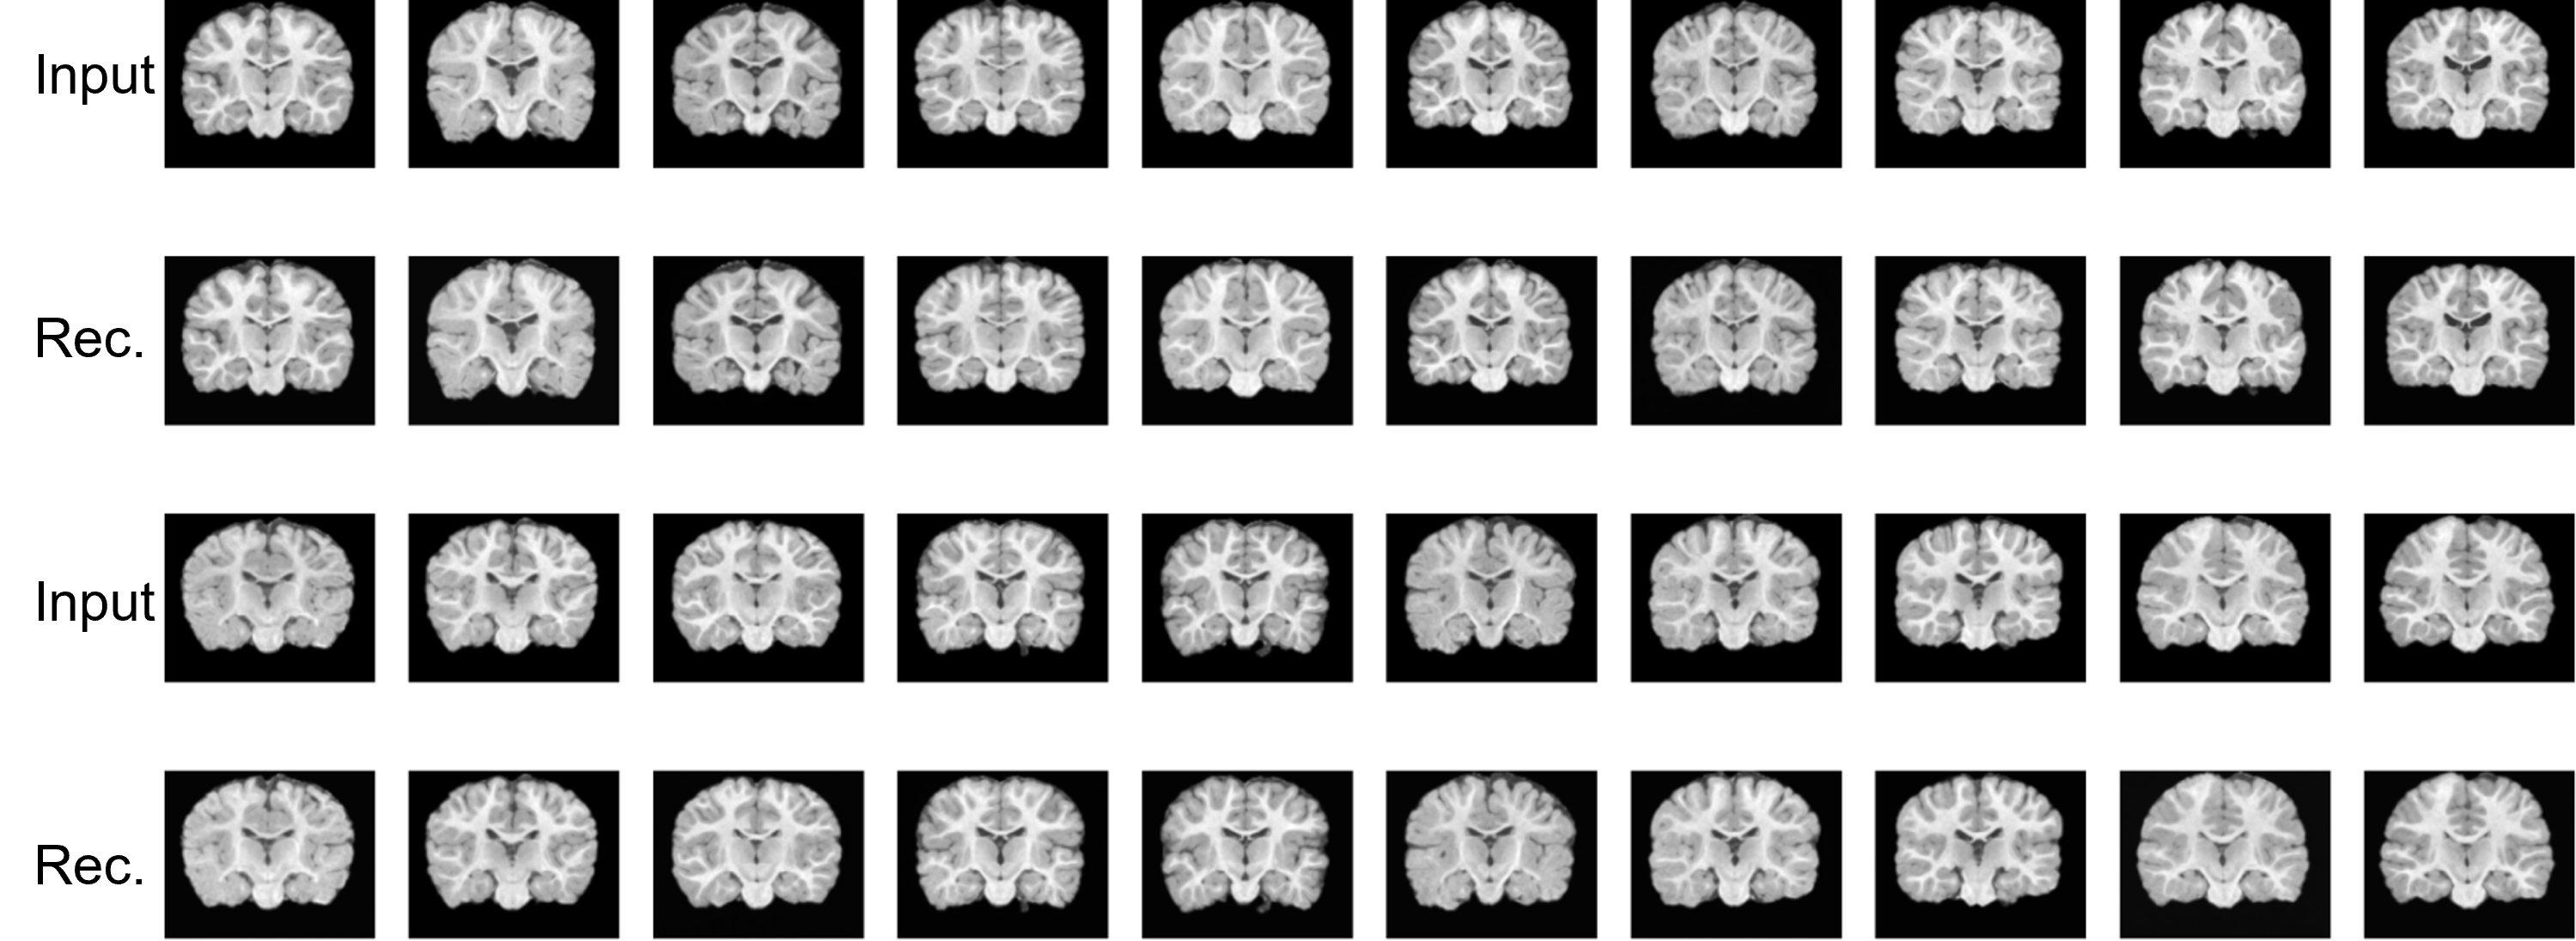

Refer to caption

Figure 4: Inputs and reconstructions of VAE trained on Baby Brain. The first and third rows display the input baby brain MR images. The second and fourth rows show the reconstructed baby brain images.

Figure 5: Inputs and reconstructions of VAE trained on OASIS-3. The first and third rows display the input OASIS-3 brain MR images. The second and fourth rows show the reconstructed OASIS-3 brain images.

In Fig. 4 and Fig. 5, we show the reconstruction results of our VAE model. The results in the figure suggest that our VAE model can faithfully reconstruct the input images. From the figure, we can observe that the VAE is able to reconstruct brain images at different developmental stages of infants. This observation aligns with the known characteristic that infant brain images are usually less defined at younger ages and become sharper as the infant grows [1].